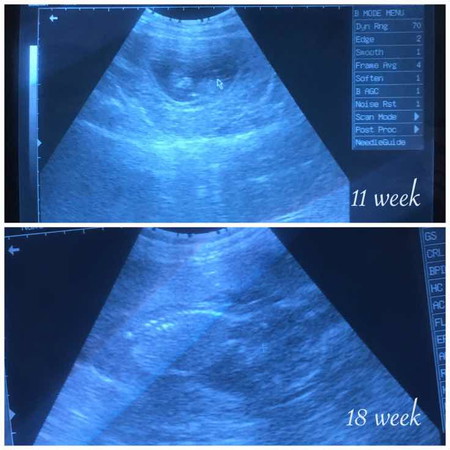

อิแม่ลุ้น?

พอแม่อยากรู้เพศนี่นอนคว่ำเลย บ้านไหนเป็นเหมือนแม่บ้าง

แม่ท้อง